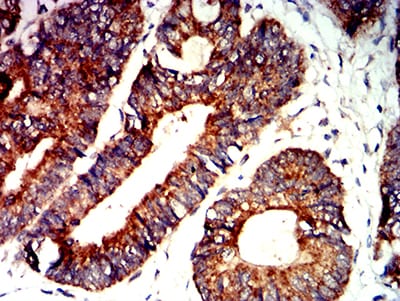

分类: 科研抗体货号: 31278别名: CTNNB; MRD19; armadillo;Beta-catenin应用: WB,IHC,FCM反应种属: Human

分类: 科研抗体货号: 31277别名: CTNNB; MRD19; armadillo;Beta-catenin应用: WB,IHC,FCM反应种属: Human,Mouse